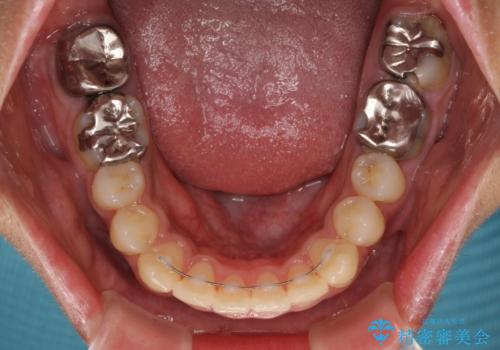

- 前歯のデコボコと八重歯、開咬を気にして来院された患者様です。

骨格的に下顎骨が上顎骨に対して後退位であったため、上顎の左右第一小臼歯を抜歯し、デコボコを改善するとともに開咬を改善していくこととしました。

舌の突出癖により開咬となっていたため、突出癖改善のためのトレーニングをしっかりと行っていただき、予定の期間で無事に治療を終えることができました。